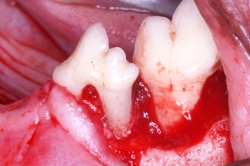

Los problemas que aquejan los tejidos periodontales son varios aunque su etiología primaria siempre es la misma, el alimento y las bacterias que se pegan a los dientes formando la placa dento bacteriana (PDB) y el sarro que destruyen lentamente pero de manera progresiva los tejidos de sostén dental. La enfermedad periodontal es la enfermedad de mayor incidencia y prevalencia en perros y gatos por lo que su diagnóstico, prevención y tratamiento es uno de los retos que el médico veterinario tiene en su trabajo clínico. La enfermedad periodontal es la causa más común de enfermedades como endocarditis bacteriana y artritis infecciosa por lo que el propietario y médico tratante deben de tener especial interés en la prevención y tratamiento de esta patología. La enfermedad periodontal se clasifica dependiendo de los tejidos afectados así como según el grado de destrucción del tejido óseo. Según el tejido afectado como “Gingivitis” cuando afecta la encía libre y papilar, y “Periodontitis” cuando ya afecta el tejido óseo y el ligamento periodontal formando destrucciones del hueso alveolar muy características de la enfermedad denominadas bolsas periodontales las cuales según la forma de destrucción pueden clasificarse como horizontales o verticales. La periodontitis se diagnóstica con una sonda periodontal que es un instrumento que tiene líneas de medición en su punta de trabajo y que se introduce en el surco gingival para medir en milímetros la destrucción ósea alveolar. Otro método de diagnóstico es la radiografía periapical en la cual se puede observar claramente el grado y forma de destrucción ósea alveolar.